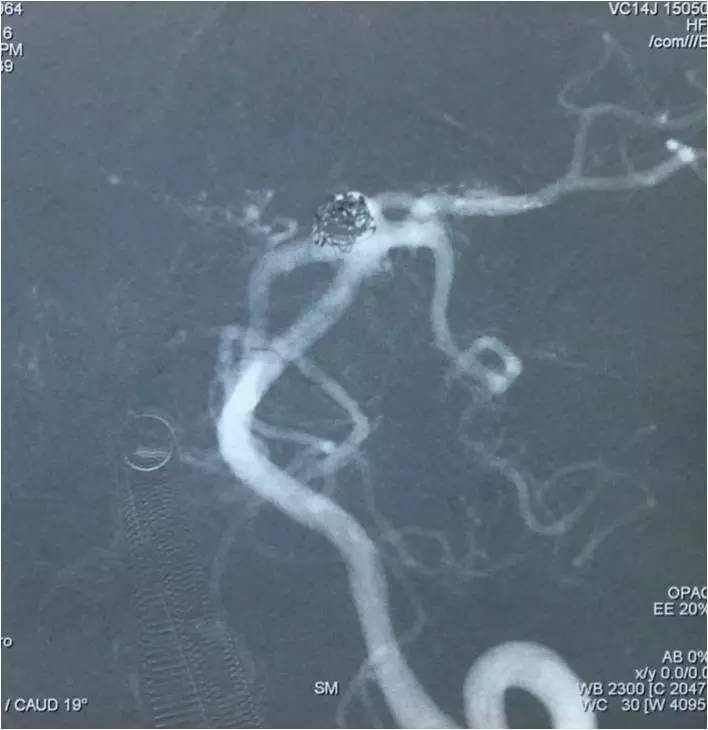

以下图像为DSA,显示基底动脉顶端动脉瘤,左侧小脑上动脉瘤,左侧PCA P1段微小动脉瘤,双侧颈内动脉眼动脉以远闭塞,前循环靠后循环通过后交通动脉代偿。

▼左椎动脉造影正位

▼左椎动脉造影侧位

▼左椎动脉造影三维重建,这个角度可以窥清基底动脉顶端动脉瘤和左小脑上动脉瘤,可见基底动脉顶端动脉瘤顶端的子瘤,考虑是SAH的责任动脉瘤。

▼这个角度可以看到左PCA P1段的微小动脉瘤